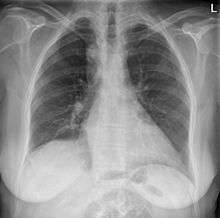

During pregnancy, prenatal ultrasound may reveal the abnormal course of the arch. On chest radiography, a right-sided aortic arch is visualized by the aortic knob (the prominent shadow of the aortic arch) that is located right from the sternum instead of left. Complex lesions are often assessed by MRI or CT.